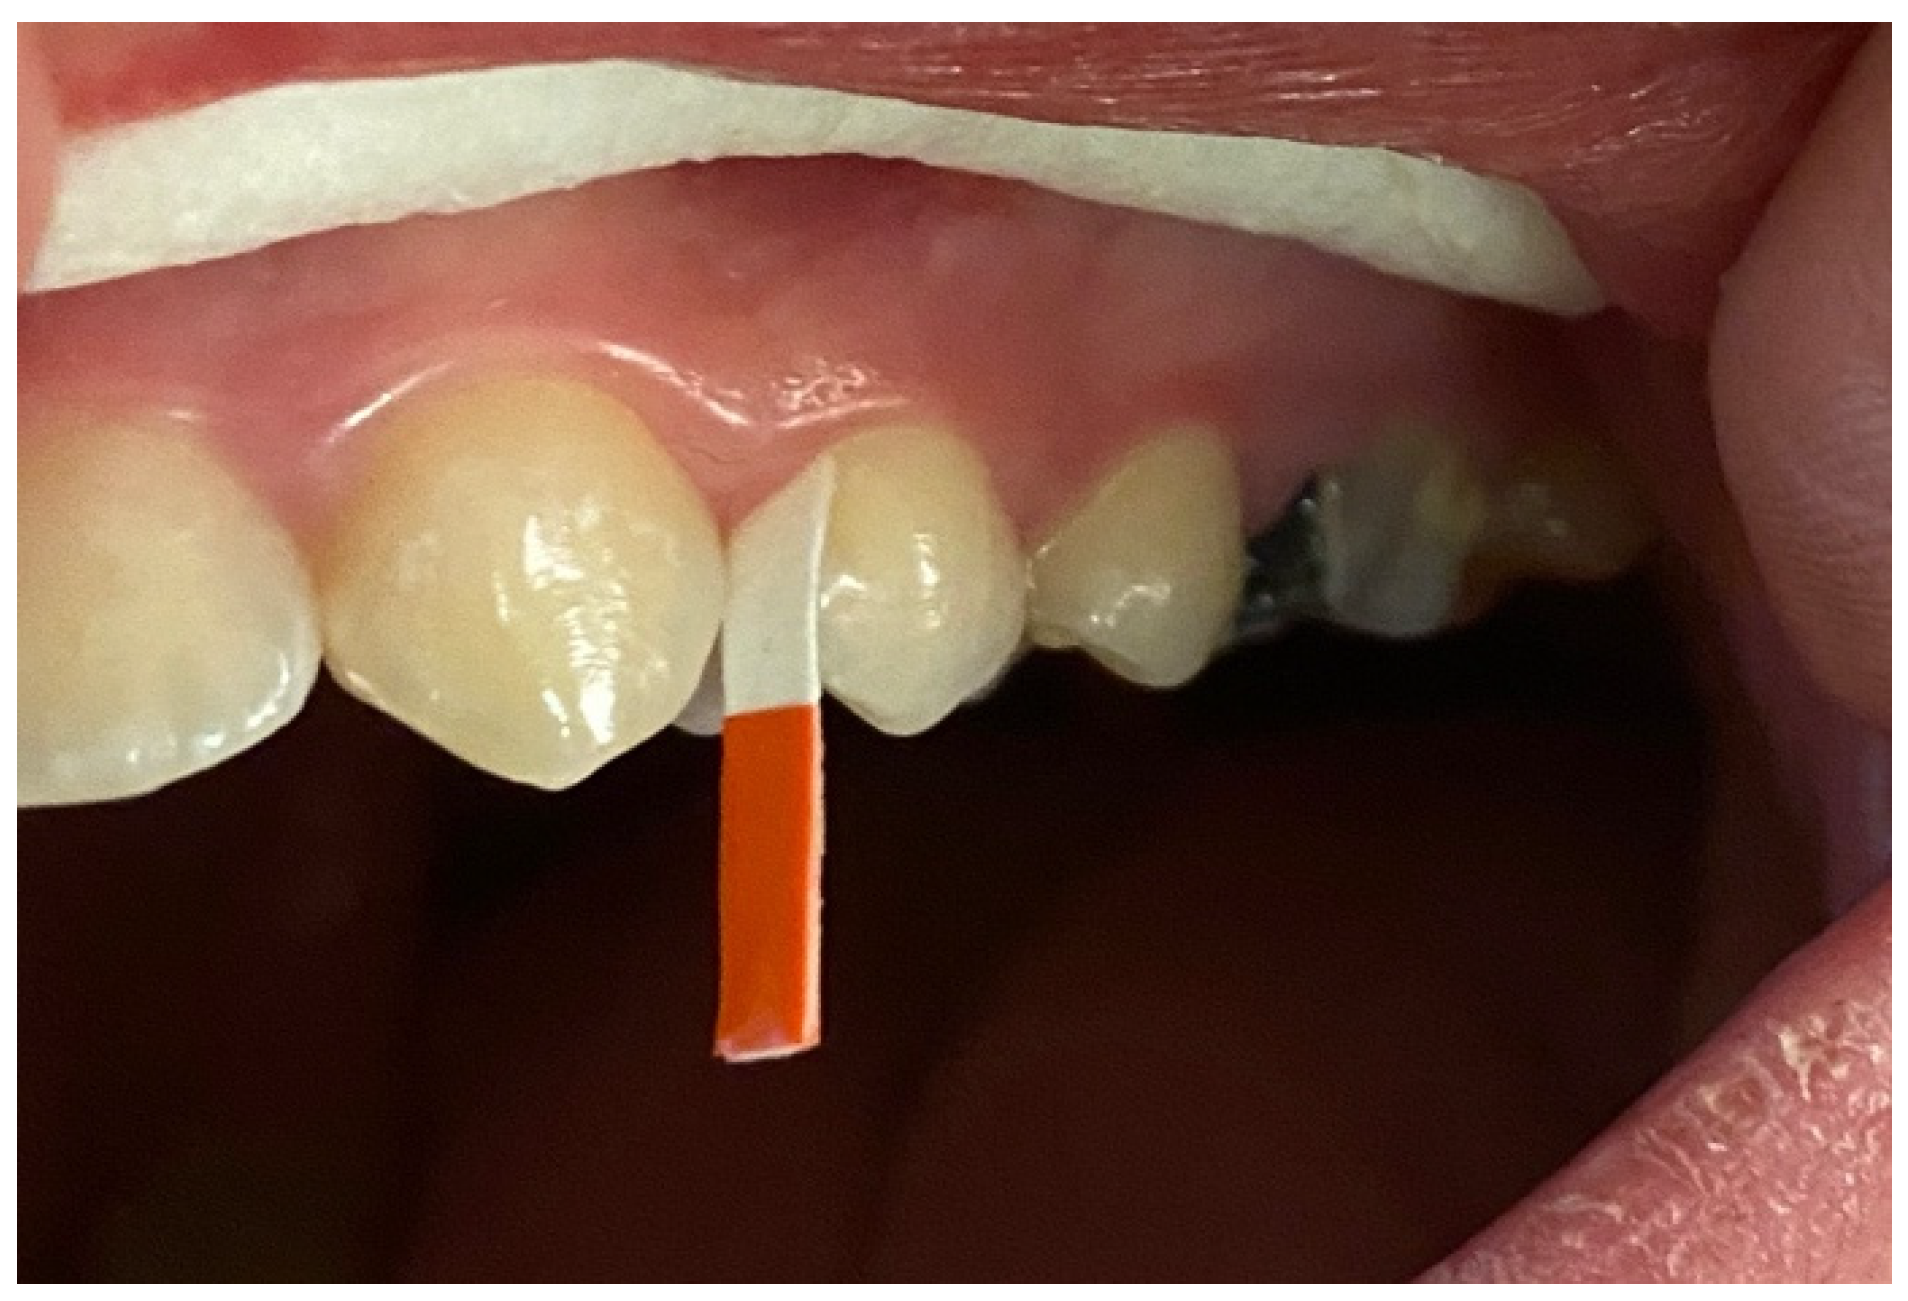

2.4. GCF Samples Collection and Analysis